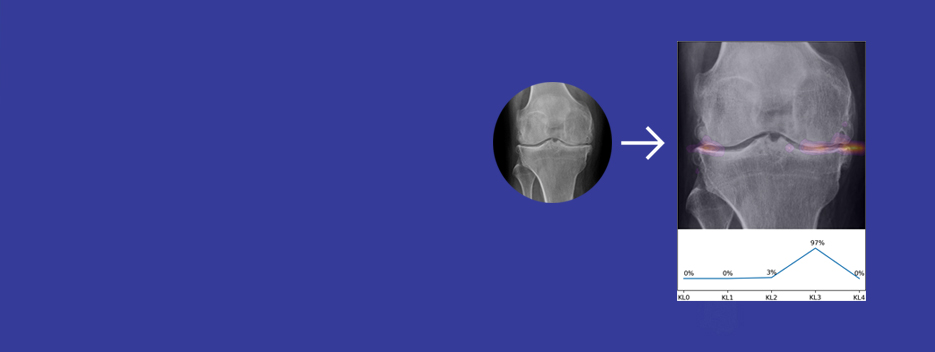

READ MOREOnce your surgeon has selected the implant that most closely matches the size and shape of your knee, adjustments are made during surgery to fit the implant to your knee joint.